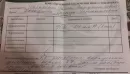

Во вторник, когда я лег спать, очень сильно разболелся зуб в районе 37-38. Не мог всю ночь спать, лез на стену, дома обезболивающих нет, т.к. не приходилось принимать. На следующий день сделал панорамный снимок, на 2 день попал к своему стоматологу. Врач сказала сделать ЭОД и 2 пути решения: